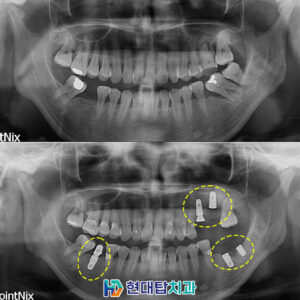

울산동구임플란트 잘하는곳 어디로 가야 할까   세월이 흘러갈수록 신체는 기능이 약해지고 여러 가지 질환이 발생합니다. ​ 치아 역시 예외는 아니며, 노화로 인해 치아가 흔들리거나 빠지게 되는 경우가 있는데요. ​ 이러한 원인으로 인해 치아를 상실하게 되면 생각보다 많은 불편함을 가져오게 됩니다. ​ 저작기능이 저하되어 소화에 문제가 발생하고, 올바른 발음을 구사하기 힘들어지는 더보기…

울산동구치과 임플란트의 튼튼한 사용을 위해   우리는 치아를 하루에 수백 번 이상 사용하고 있습니다. ​ 그만큼 삶의 질을 좌우하는 중요한 부분 중 하나로 음식물을 씹어서 필요한 영양분을 신체에 공급할 수 있도록 해줍니다. ​ 하지만 충치나 치주 질환, 노화, 외상, 사고 등과 같은 다양한 이유로 치아의 손상이나 상실을 맞이하게 될 수 더보기…

울산동구치과 고민하고 있다면 ​ 치아는 통증이 느껴지지 않으면 관리에 소홀해지기 쉽지만 건강하고 행복한 삶을 위해 구강건강관리는 필수적으로 해주어야 합니다. ​ 치아가 건강하지 못하면 음식물 섭취가 원활하지 못해 소화기관의 부담이 늘어나고 발음이 ​ 어눌해지면서 의사소통에 어려움을 겪을 수 있고 또한, 치아의 저작기능은 뇌의 활동에도 영향을 주기 때문에 집중력과 기억력 저하의 문제로 더보기…